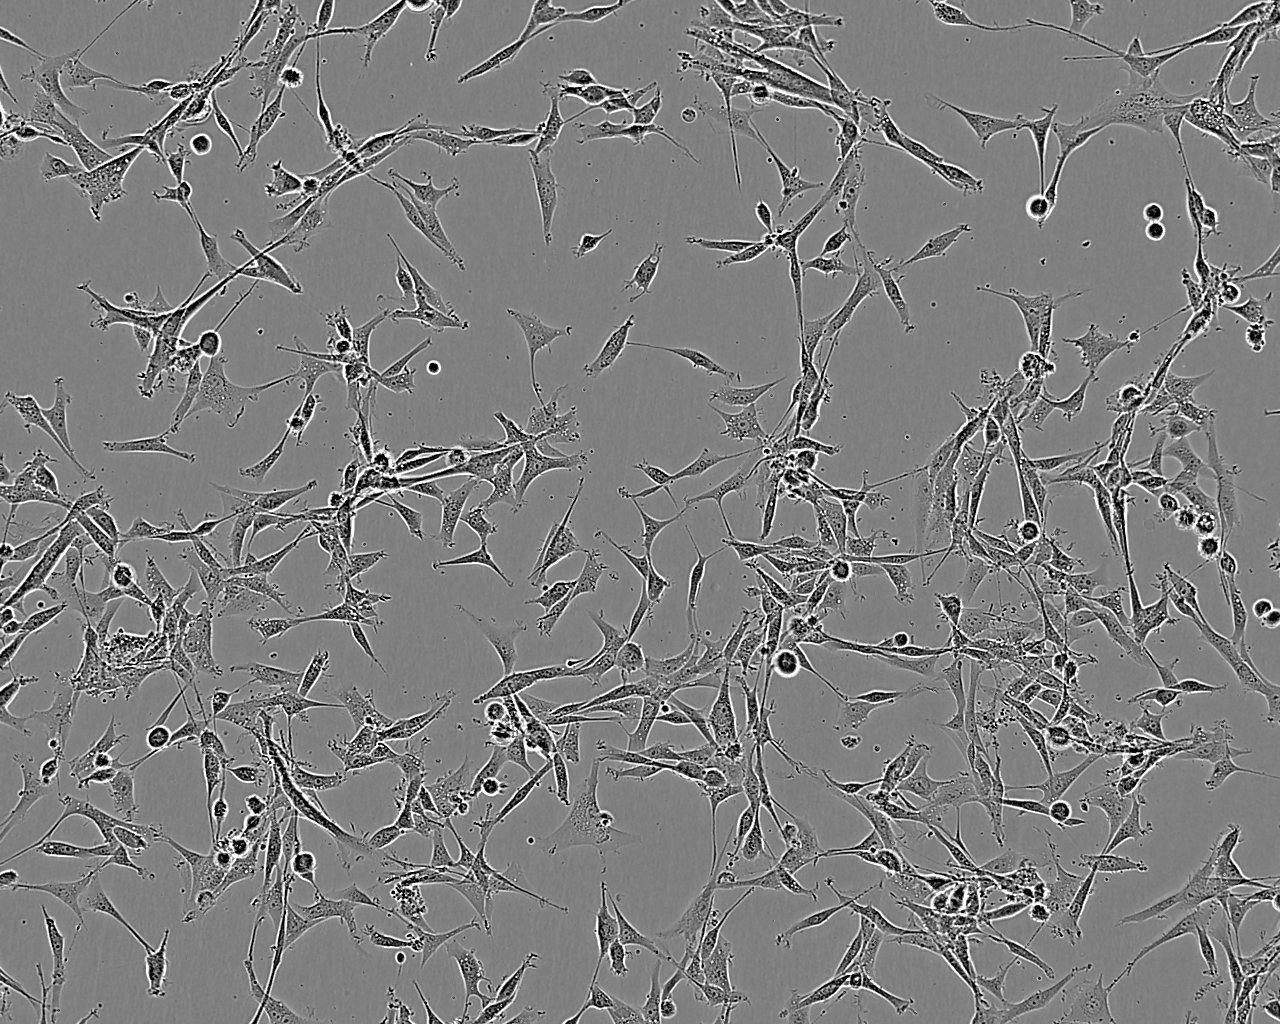

细胞背景资料:TT细胞由LeongSS等,自一位77岁白人女性甲状腺髓样癌患者的穿刺活检样本中建立。TT细胞持续产生高水平的降血素和CEA。更换培养基后24h和72h,在培养基中检测到的免疫活性的降血素浓度分别为3900pg/106个细胞和7700pg/106个细胞。72小时后CEA积累浓度超过27ng/106个细胞;该细胞最初是在RPMI1640培养液中培养,可产生神经肽,但还不知道在F12培养液中培养是否会产生。

细胞形态:上皮细胞样

细胞生长:贴壁

细胞生长特性:贴壁生长